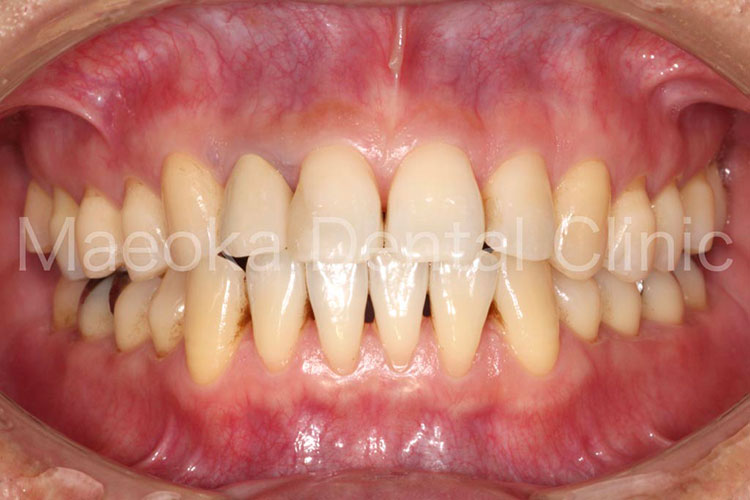

患者さんは58歳の男性の方で、「右下の歯がグラグラして痛いので診て欲しい」という主訴で来院されました。お口の中を拝見すると重度の歯周病を認めました。1日1箱近い本数の喫煙があったこともあり、歯肉は血行不良を起こして黒っぽい印象がありました。

初診時には歯周病の原因と「どうすれば歯周病は治るのか」、「再発を防ぐためには何が必要なのか」を説明し、歯磨きのトレーニングをスタートしました。その後、患者さんのプラークコントロールレベルが向上したタイミングで歯石を取り、基本治療を終えました。その後、義歯を入れるなどの機能回復も検討しましたが、患者さん自身が不都合を感じていなかった点、レントゲン上でも残存歯の負担が増加している所見が見られなかった点を考慮し、経過観察としています。

主訴の右下7は失うことになってしまいましたが、その他の歯は現在のところ1本も失うことなく経過しています。現在も喫煙はありますが、歯肉は引き締まり、健康な組織を取り戻しています。今後はメインテナンスを通してプラークコントロールレベルの維持に患者さんと取り組んでいきます。

治療前(正面)

治療後(正面)